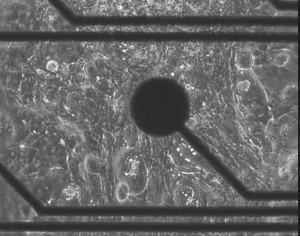

In recent decades, significant progress has been made in the treatment of heart diseases, particularly in the field of personalized medicine. Despite the development of genetic tests, phenotyping and risk stratification are performed based on clinical findings and invasive in vivo techniques, such as stimulation conduction mapping techniques and programmed ventricular pacing. Consequently, label-free non-invasive in vitro functional analysis systems are urgently needed for more accurate and effective in vitro risk stratification, model-based therapy planning, and clinical safety profile evaluation of drugs. To overcome these limitations, a novel multilayer high-density microelectrode array (HD-MEA), with an optimized configuration of 512 sensing and 4 pacing electrodes on a sensor area of 100 mm2, was developed for the bioelectronic detection of re-entry arrhythmia patterns. Together with a co-developed front-end, we monitored label-free and in parallel cardiac electrophysiology based on field potential monitoring and mechanical contraction using impedance spectroscopy at the same microelectrode. In proof of principle experiments, human induced pluripotent stem cell (hiPS)-derived cardiomyocytes were cultured on HD-MEAs and used to demonstrate the sensitive quantification of contraction strength modulation by cardioactive drugs such as blebbistatin (IC50 = 4.2 μM), omecamtiv and levosimendan. Strikingly, arrhythmia-typical rotor patterns (re-entry) can be induced by optimized electrical stimulation sequences and detected with high spatial resolution. Therefore, we provide a novel cardiac re-entry analysis system as a promising reference point for diagnostic approaches based on in vitro assays using patient-specific hiPS-derived cardiomyocytes.